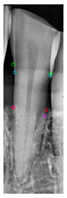

2.6.1. Retained the Largest Mask

Three different mask categories are obtained from the Mask R-CNN prediction results: Tooth Mask, Bone Mask, and Crown Mask. After acquiring these masks, only the fully segmented teeth are analyzed. For the incomplete teeth within the Tooth Mask, the neighboring Tooth Mask needs to be addressed. Since YOLOv8 was used earlier to extract individual teeth, each Tooth Mask contains one complete tooth, covering most of the area, allowing the removal of the masks of any incomplete teeth, as shown in Figure 7a,b.

Figure 7.

Mask R-CNN predictions for single tooth and Tooth Mask processing. (a) Mask R-CNN prediction. (b) The mask predicts the result. (c) Removing incomplete Tooth Mask.

Instance segmentation not only requires detecting the object’s class and location but also involves pixel-level segmentation for each object, each object is segmented into a unique region, even if they belong to the same class. The study identifies all pixel values within the Tooth Mask and saves the masks predicted by Mask R-CNN, representing the pixels of the same object with the same value. The number of different pixel values is then calculated and the pixel value with the largest area is recorded. Other objects with different pixel values are removed, as shown in Figure 7c. This method ensures that only the complete Tooth Mask is used for analysis, thereby improving diagnostic accuracy and efficiency.